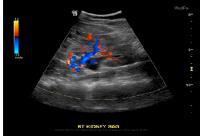

بیماری کلیوی

بیماری‌های کلیوی یکی دیگر از دلایل بروز ادرار خونی به شمار می‌رود که می‌تواند به تنهایی یا به عنوان بخشی از بیماری دیگری همچون دیابت اتفاق بیفتد.

هرآنچه لازم است درباره سونوگرافی کلیه بدانید